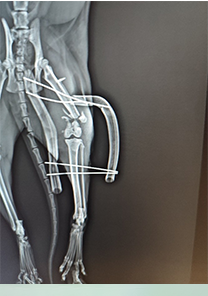

Veysel Bey'in Kedisi Paşa

Veysel Bey'in kedisi Paşa'nın tibiave fibulasının proksimalinde distal kırık tespit edilmiştir. Operasyon günü itibarıyla MN - HUND&KATT kullanılmıştır. Operasyondan sadece 14 gün sonra eksternal fiksatör takılan kediden pinler çıkarılmış ve tamamen iyileşmiştir.